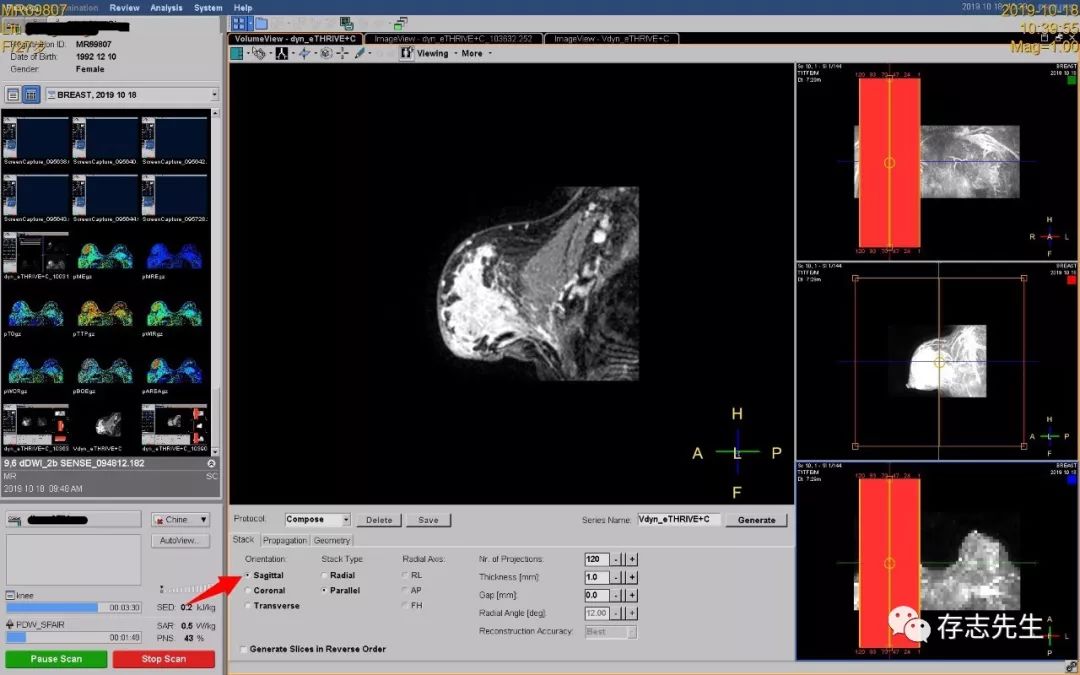

4、动态增强MPR多方位重建,选择重建的方向、层厚、层数;

矢状位仍然选择一侧一侧的重建,便于观察;